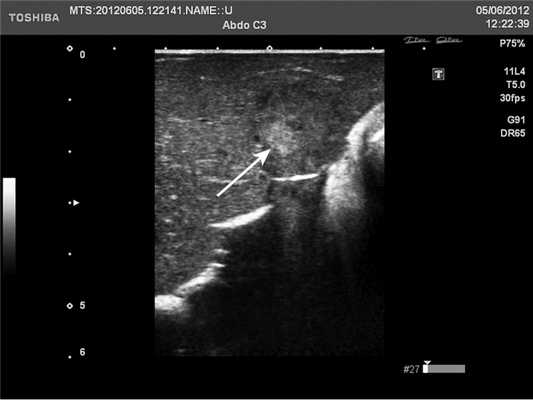

У 5 (41,7%) из 12 пациенток образования в печени имели гиперэхогенную, гомогенную структуру с четкими и ровными контурами размером от 5 до 12 мм в диаметре, которые были интерпретированы как доброкачественные образования печени — гемангиомы (табл. 2). У 4 (33,3%) пациенток образования имели анэхогенную гомогенную структуру, с четкими и ровными контурами, с гладкой внутренней выстилкой и эффектом усиления эхосигнала, размером от 3 до 11 мм в диаметре, и были интерпретированы как кисты. В 3 (25%) случаях в печени были выявлены гипоэхогенные образования солидной гетерогенной структуры с нечеткими, но ровными контурами размером от 10 мм в диаметре (рис. 1) до 22×17×15 мм в одном случае, расположенное на диафрагмальной поверхности печени, которое «самоампутировалось» в процессе исследования и при срочном гистологическом исследовании оказалось метастазом аденогенного рака (рис. 2).

Рис. 1. Эхограмма. Интраоперационное УЗИ печени (стрелкой указан метастаз рака яичника).